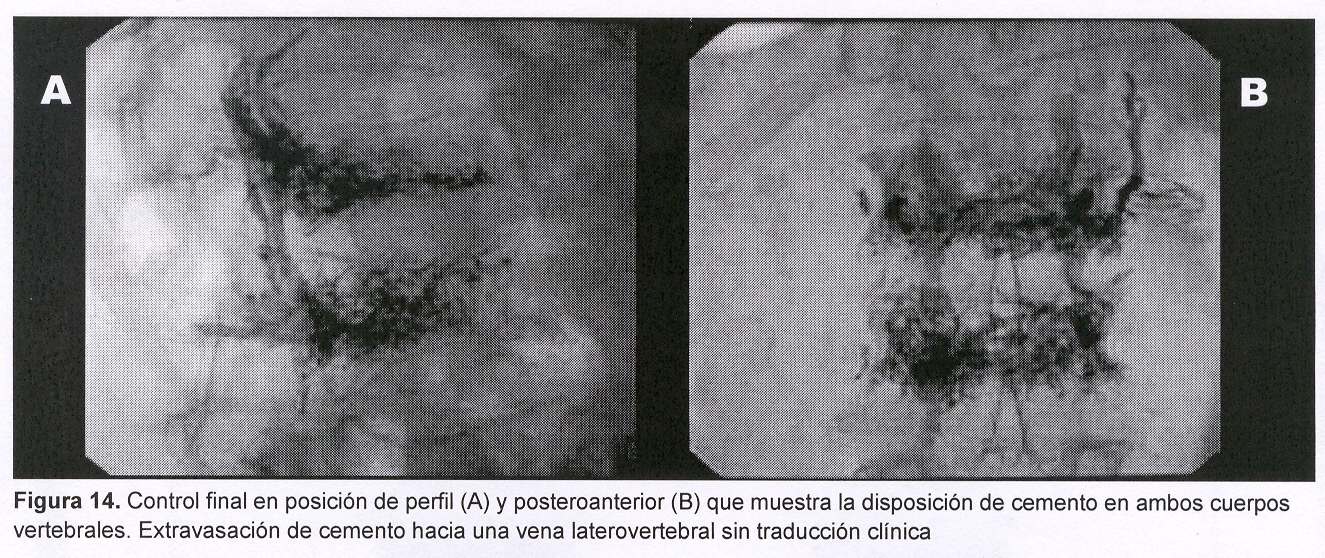

Sexo femenino, 67 años, con dolor raquídeo dorsolumbar de varios meses de evolución. En los últimos 15 días nota aumento de la intensidad del dolor, que la obliga a mantener reposo en cama en forma permanente a pesar del tratamiento médico. Sin sintomatología radicular. Se realizó radiografía y TC de región dorsolumbar que mostró: desmielinización difusa y fractura por aplastamiento de L1 y L2 con disrupción parcial de los muros posteriores.

La paciente es tratada en forma ambulatoria (figuras 13 y 14), a las 12 horas del procedimiento el dolor raquídeo comenzó a disminuir para desaparecer completamente a la semana.

Durante la inyección la fuga de cemento a lo largo del curso de la aguja puede determinar compresión de la raíz nerviosa y dolor radicular. Por este motivo se prefiere la vía transpedicular siempre que sea posible. La fuga de cemento a venas laterales o anteriores o al disco intervertebral normalmente no tiene consecuencias clínicas. De todas formas ante una fuga a vena, la inyección se detiene inmediatamente para evitar el embolismo pulmonar(21). En este caso puede continuarse el tratamiento luego de haber esperado unos segundos, o luego de avanzar o rotar ligeramente el trocar.